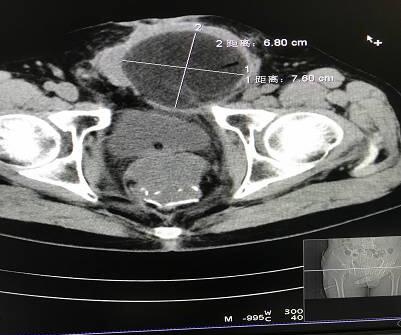

冷冻消融前,CT上健下腹部肿块,压迫膀胱